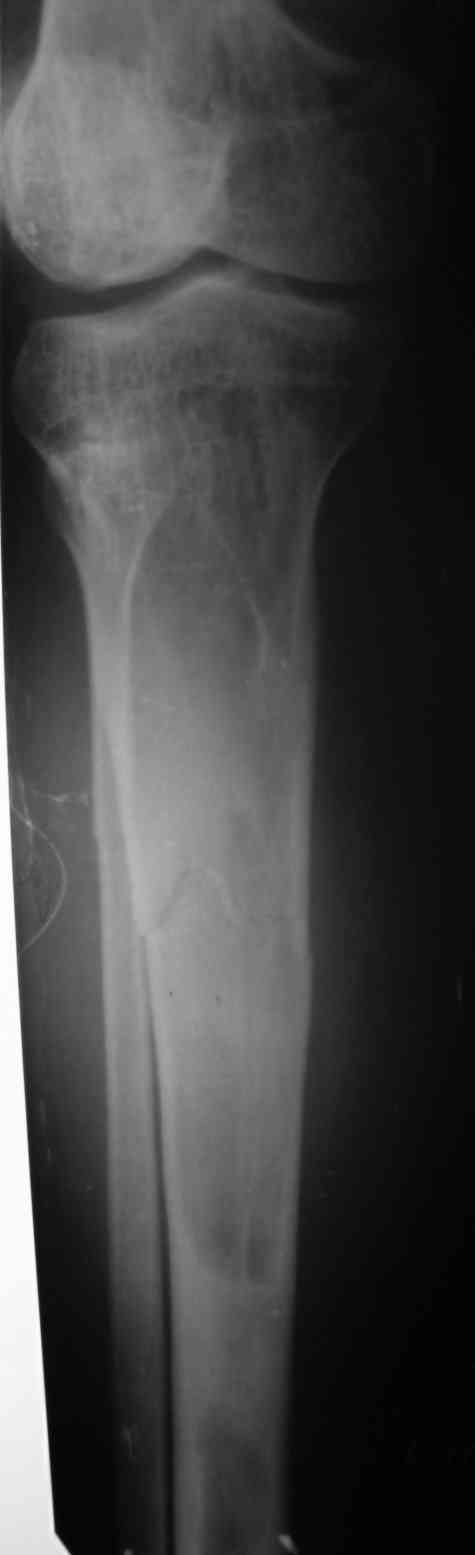

Re: Патологический перелом костей голени.

Вторая проекция.

Если это фиброзная дисплозия, зачем выполнять экскохлеацию? Это не опухоль. Достаточно провести остеосинтез (лучше БИОС). Травма стимулирует остеогенез и произойдет спонтанная оссификация в зоне перелома. Пациент прожил 20 лет без экскохлеации. При полиоссальной форме фиброзной дисплазии не принято радикально лечить один из очагов. Другие все равно останутся. В отношении дополнительной пластики высказаться затрудняюсь, может быть стоит. И если она будет выполняться, следует выполнить и биопсию содержимого полости в зоне перелома для исключения ОБК.

Костная пластика фиброзной дисплазии обречена на неудачу. Ткань фиброзной дисплазии преобладает над нормальной костью через несколько лет. Переломы при фиброзной дисплазии заживают так же, как и обычные. Так что обычного гвоздя будет достаточно. Это защитит кость от переломов в будущем. Вероятность преобразования в остеосаркому порядка 4-ёх процентов. Так что имеет смысл следить за пациентом на протяжении всей жизни.

Доброго времени суток. Всем участвовашим большое спасибо за советы и предложения. Вчера выполнили рассверливание КМК и БОИС большеберцовой кости 11 мм штифтом. С уважением, Евгений.